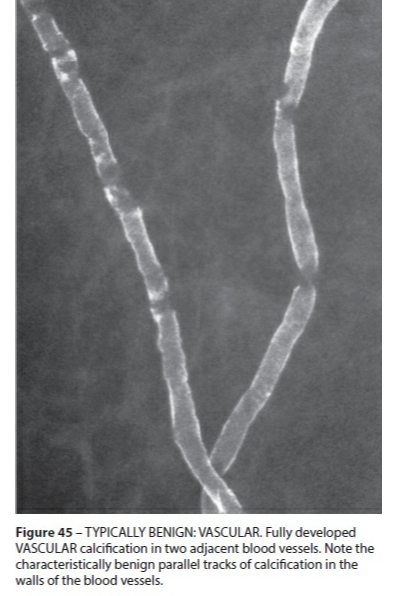

Calcifications vasculaires

- Parallèles en rail ou tubulaires linéaires

- Si doute → Magnification